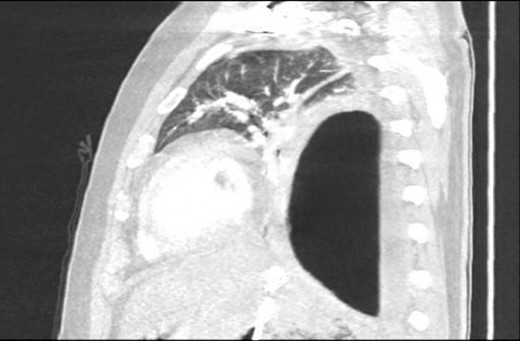

Chest X-ray in ICU following drainage showed what was thought to be Pneumomediastinum (Figs 1 and 2), and given this concern he was referred to the Cardiothoracic service. Subsequent CT suggested a large loculated hydro-pneumothorax, which in retrospect represented the drained Pseudocyst communicating through the diaphragm (Figs 3 and 4).

Sagittal view CT Chest revealing large residual space with loss of left lung volume due to the pseudocyst. Image post-transgastric drainage.